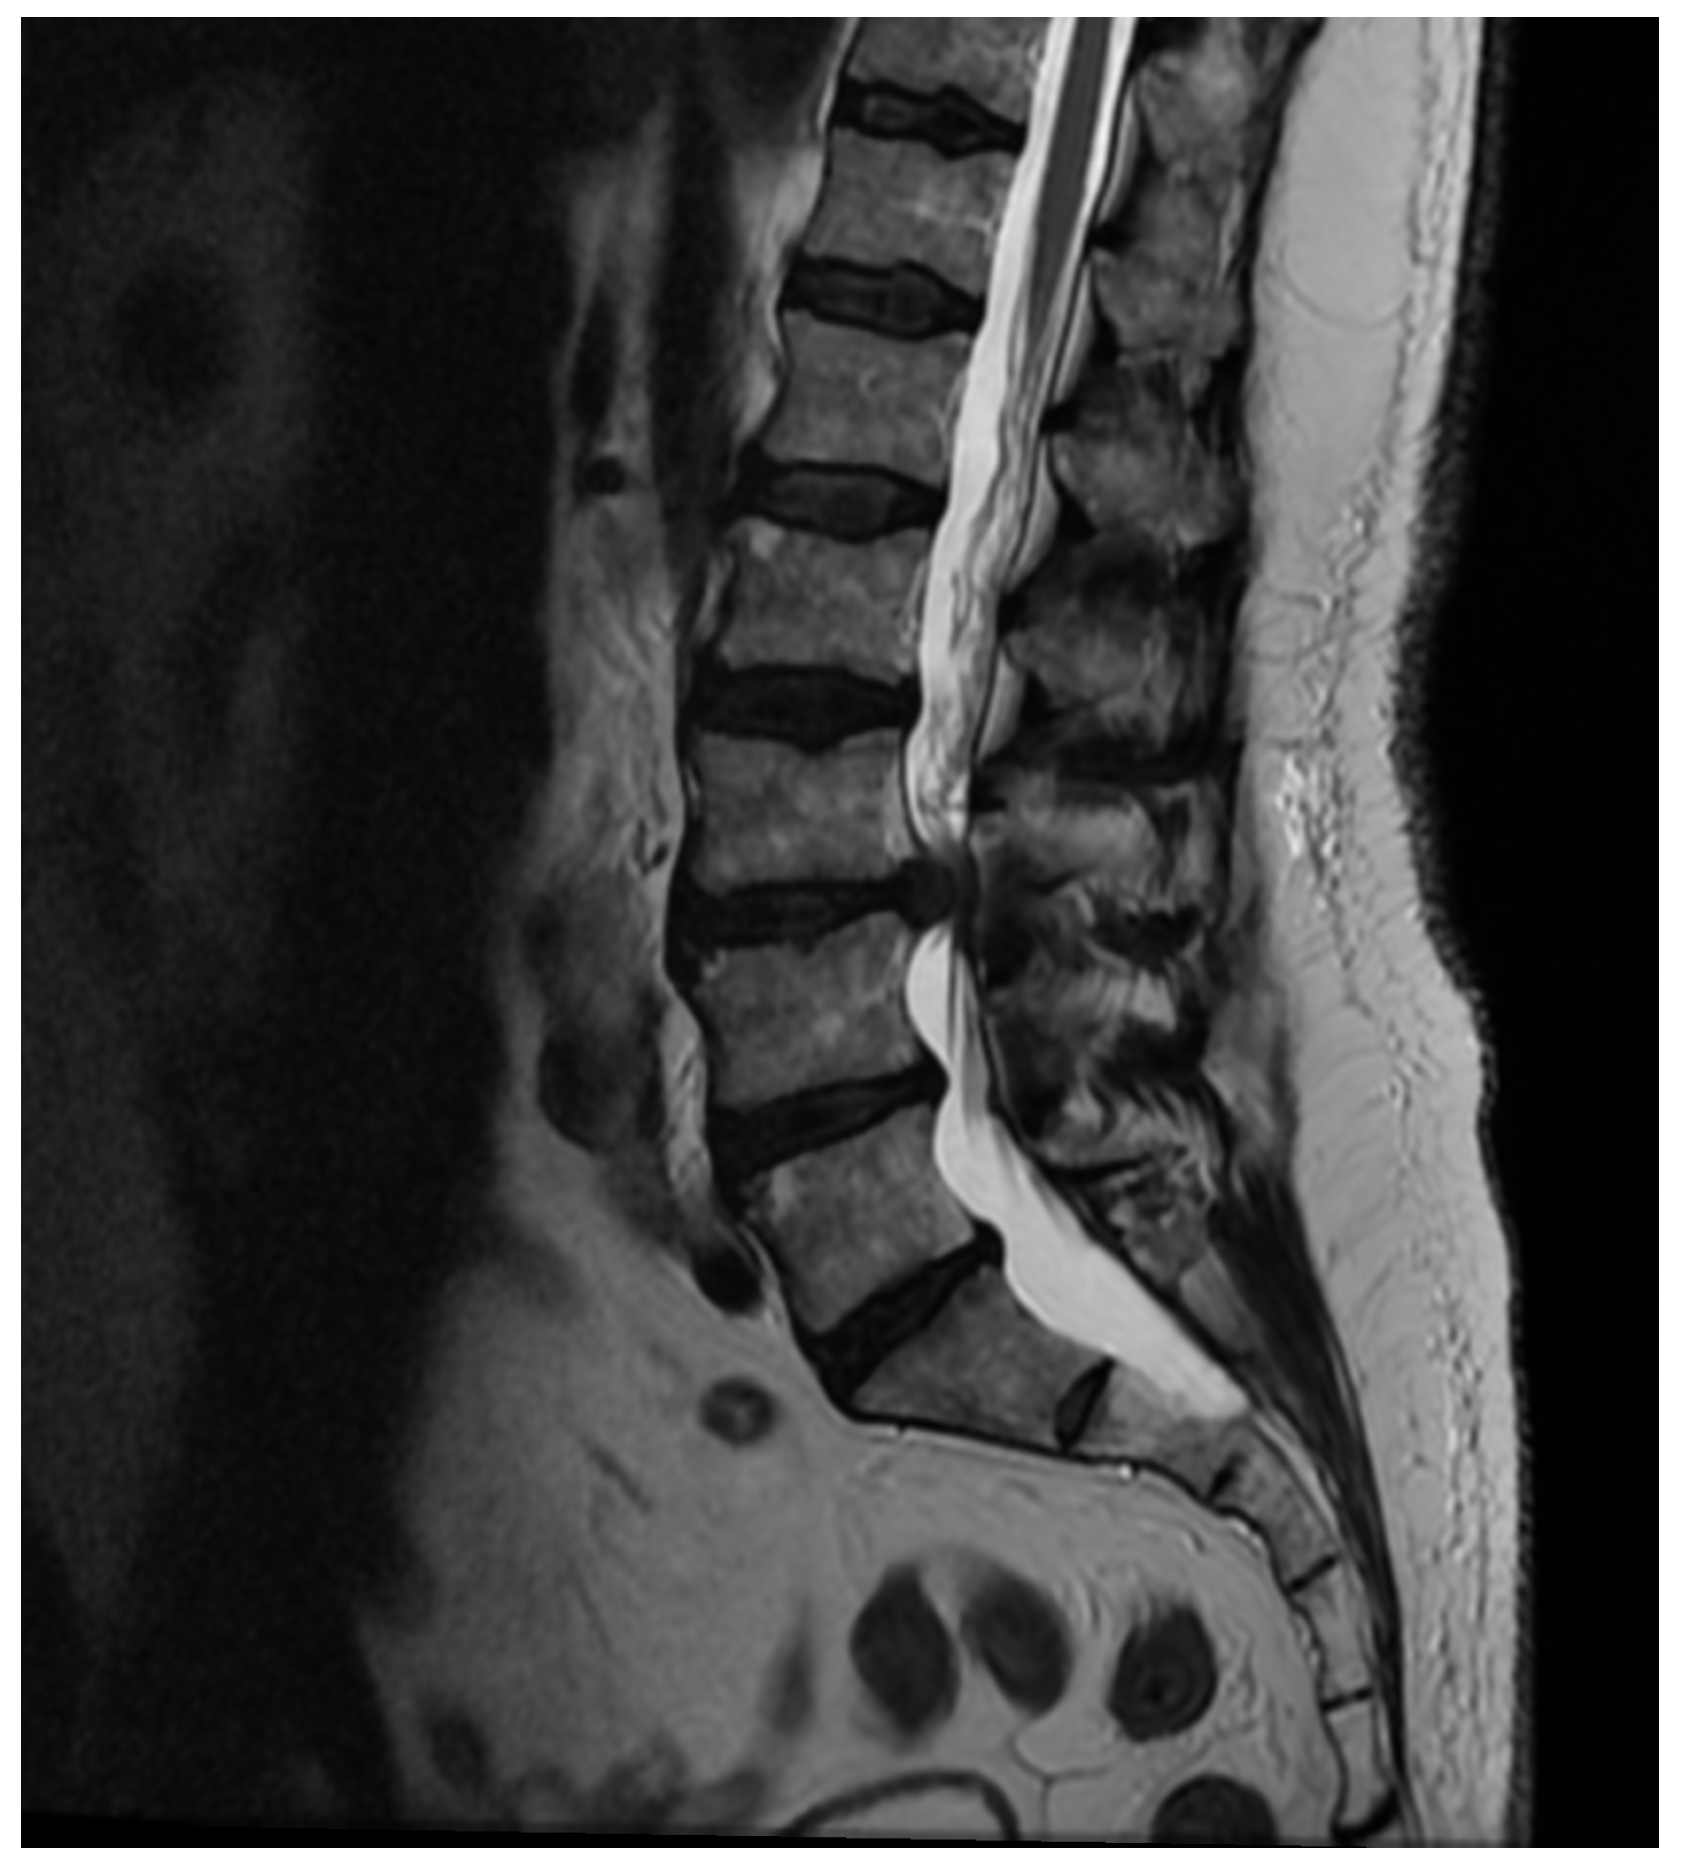

Patient Background: A 50-year-old female patient with a body mass index (BMI) of 32 was admitted to the neurology emergency department due to an acute spinal pain syndrome persisting for three days. The pain, VAS 7, was located in the lower spine, radiating bilaterally to both lower limbs, and exacerbated by movement. The patient had undergone a gynecological procedure under epidural anesthesia one month prior to this episode. Initial MRI (Figure 2) of the spine revealed a collapse of the L5/S1 space with a small central protrusion. The disc signal raised suspicion of early inflammatory changes in the eyes of the consulting neurosurgeon, though the radiologist conclusively denied inflammatory features. The patient presented with slightly elevated inflammatory markers, with a CRP level of 20 mg/L.

Figure 2. Pre-operative T2 axial MRI image at the L5/S1 level on the day of the patient’s admission to the neurology department.